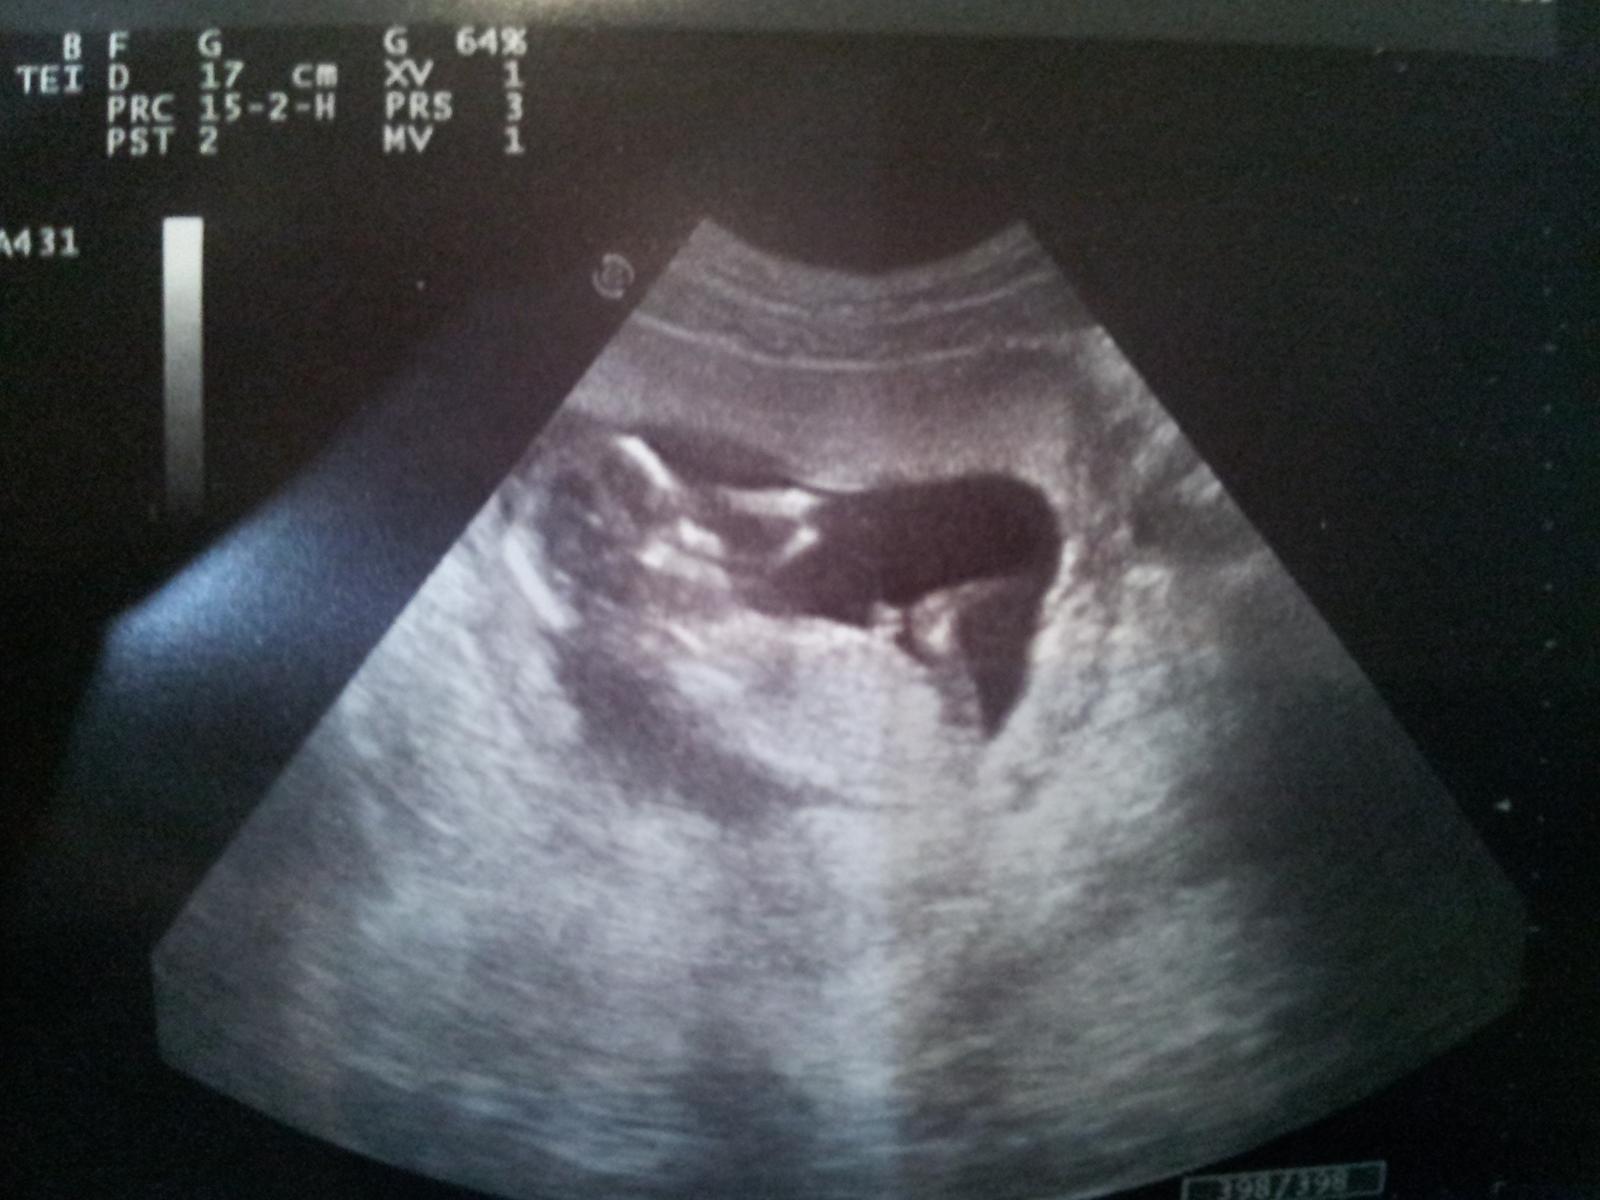

Ahojte babenky, ako sa máte? my sme dnes boli na morfologickom utz a budeme mať chlapčeka.....máme už krásnych 20,03 cm a 405 g...... a všetko je v poriadku... malý sa veľmi teší na bračeka, tak sa moc tešíme 🙂 🙂 všetkým ostatným tehuľkám a aj budúcim tehuľkám držím palčeky....... 🙂 🙂